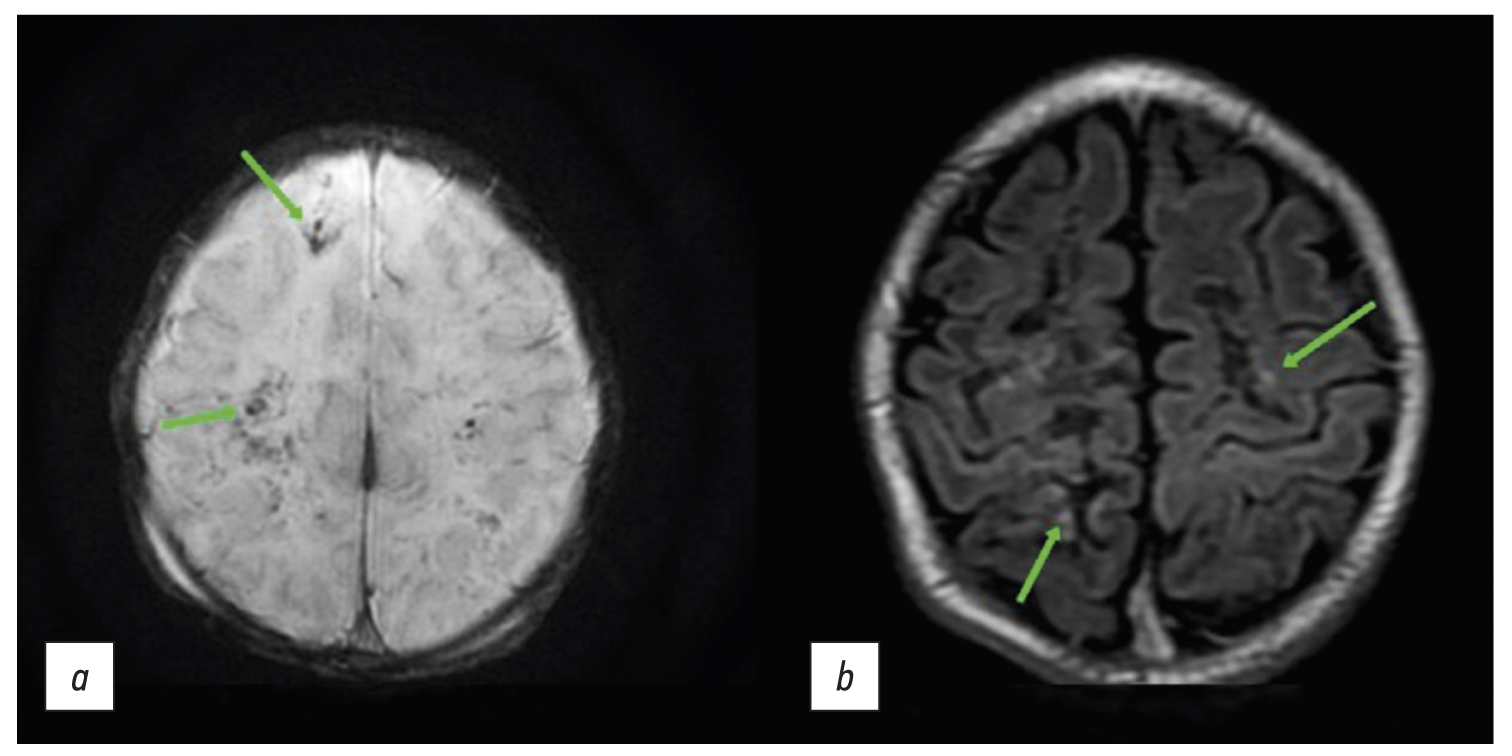

Among the numerous lesions in the presented instance, the brain MRI revealed single regions with hemorrhagic features compatible with ischemia (Figure 3а). This suggests that not all ischemia foci were accompanied by bleeding. Although necrotic areas eventually turn into encephalomalacia areas, some areas with minimal damage may recover entirely and even be consistent with the normal structure of brain matter in MRI [16]. The hyperintense signal was seen in the cortical area and at the gray/white matter interface in the frontal and parietal lobes in T1-weighted images (T1-WI) (Figure 3b). These areas resemble cortical necrosis, which occurs after ischemia damage to the cortex, resulting in monocyte infiltration and phagocytosis of cell fragments in the damaged structures. T1 images are hyperintense due to deposits of denatured protein of the dead cells and/or lipid-loaded macrophages [17].

Fig. 3. Magnetic resonance imaging (MRI) of the brain: (a) susceptibility-weighted images (the arrows show microhemorrhages) and (b) Т1-weighted images (the arrows indicate hyperintense areas of the cortical necrosis).